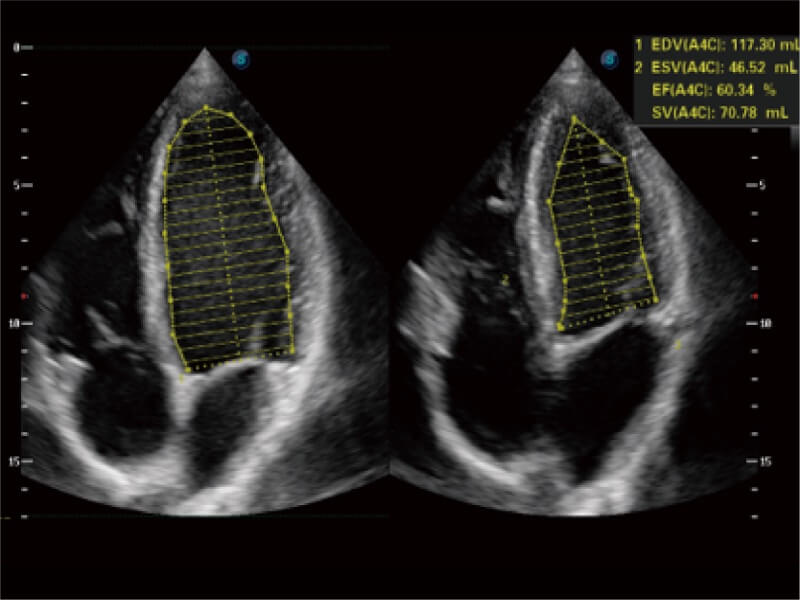

能夠基于左心室壁追蹤和辛普森法,自動計算射血分?jǐn)?shù),支持多個可移動點(diǎn)描跡,與手動測量相比,極大節(jié)省了動物醫(yī)生的時間和精力。